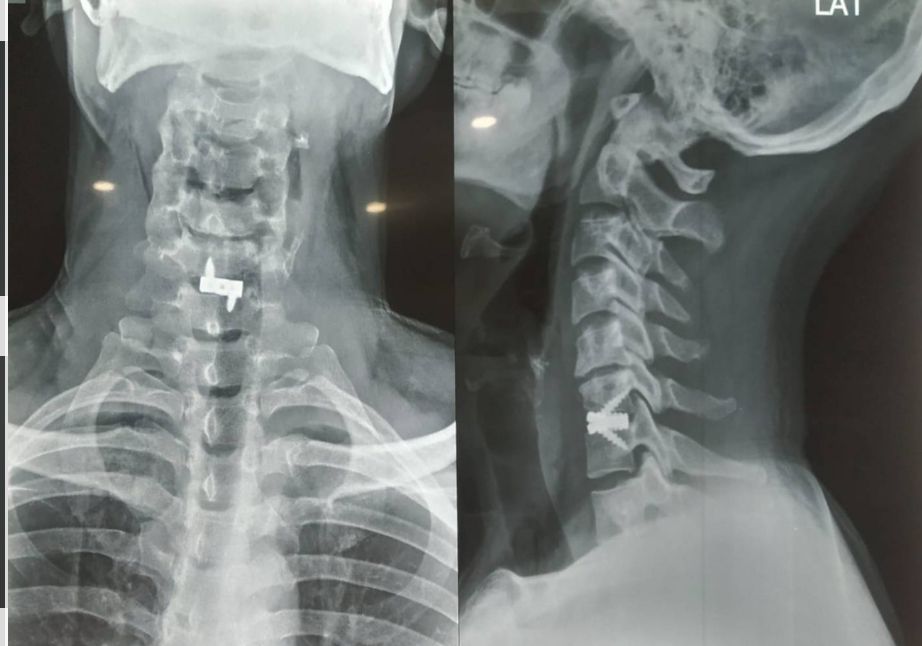

An endoscopic microdiscectomy is a minimally invasive endoscopic surgery that allows direct visualization of the disc and nerves. This procedure is used for decompressing nerve roots damaged by compressed spinal discs. It is usually indicated in patients with a herniated or compressed lumbar disc, who have not found adequate pain relief with pain management injections or conservative treatment.